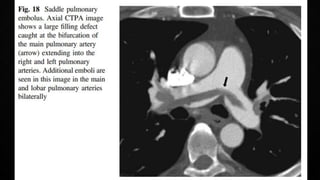

COMPUTERISED TOMOGRAPHIC PULMONARY

ANGIOGRAPHY (CTPA)

• Multidetector CTPA is the method of choice for imaging the pulmonary vasculature in

suspected PE

• PIOPED II Study (Prospective Investigation On Pulmonary Embolism Diagnosis)

observed a sensitivity of 83% and a specificity of 96%

• In patient with a low/intermediate pre-test probability, negative predictive value of a

CTPA to rule out PE was high (96%/89%), but only 60% if the pre-test probability was

high

• The positive predictive value is high (92-96%) if the pre-test probability is intermediate or

high, but much lower (58%) if the clinical likelihood was low

• Remains controversial whether patients with a negative CTPA and a high clinical

probability should be further investigated

• Pre-existing CTEPH should not be missed

COMPUTERISED TOMOGRAPHIC PULMONARY ANGIOGRAPHY(CTPA) • Multidetector CTPA is the method of choice for imaging the pulmonary vasculature in suspected PE • PIOPED II Study (Prospective Investigation On Pulmonary Embolism Diagnosis) observed a sensitivity of 83% and a specificity of 96% • In patient with a low/intermediate pre-test probability, negative predictive value of a CTPA to rule out PE was high (96%/89%), but only 60% if the pre-test probability was high • The positive predictive value is high (92-96%) if the pre-test probability is intermediate or high, but much lower (58%) if the clinical likelihood was low • Remains controversial whether patients with a negative CTPA and a high clinical probability should be further investigated • Pre-existing CTEPH should not be missed